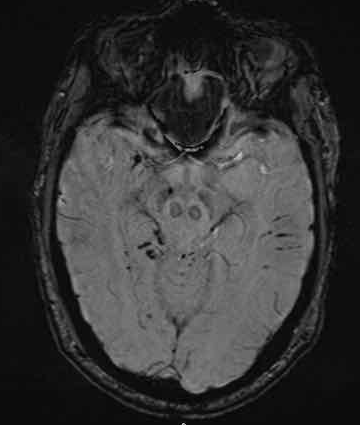

下图 一位46岁的男子骑摩托车时受伤。

瞳孔无反应性,瞳孔扩张。

CT:额叶点状出血。

继续做核磁共振成像

弥漫性轴索损伤(DAI)MRI表现

- 累及皮质下区、胼胝体、右侧丘脑和壳核、脑干、小脑脚和右侧小脑半球。

- 轻度全球萎缩。

MRI可准确诊断DAI,包括T2*GRE或SWI。

DAI在颅脑损伤患者MRI上的存在,更有可能导致不良的功能结局。